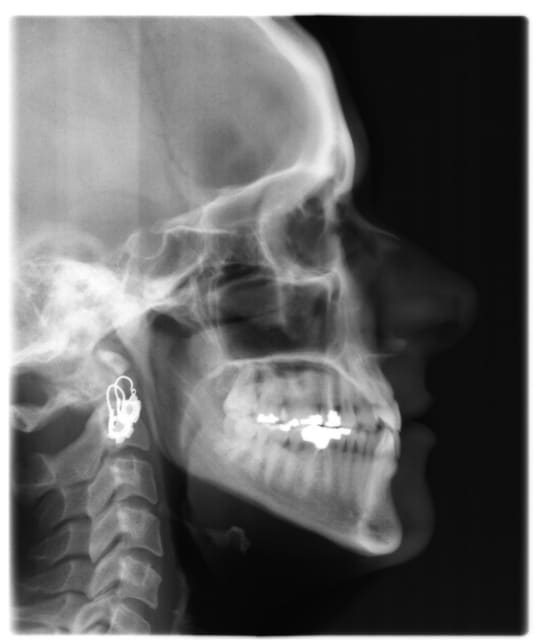

voici de la cas d'un jeune dame de 23 ans qui présente une full classe III subdivision Droite (associée à des compensations incisives de classe III), sur un terrain hyperdivergent. on note un encombrement inferieur d'environ 2 mm et une abrasion des bords triturants des incisives inf (Motif de la consultation)

on notera egalement de face une déviation de la pointe du menton vers la gauche.